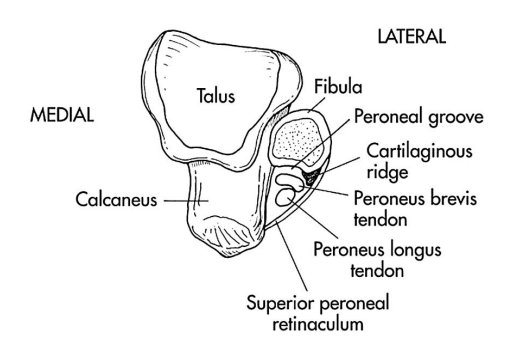

损伤分级

Ⅰ 级:占 51%,腓骨上支持带连同骨膜从腓骨上撕脱,腓骨肌腱突破纤维软骨脊滑脱至假囊中; Ⅱ 级:占 33%,腓骨上支持带和纤维软骨脊一起撕脱,肌腱脱位于纤维软骨脊下; Ⅲ 级:占 16%,腓骨上支持带附着的皮质骨撕脱骨折,且肌腱移位至撕脱骨片下; Ⅳ 级:最罕见,腓骨上支持带自后方止点处完全撕脱损伤,腓骨肌腱移位到腓骨上支持带外。

图源:DOI:10.1302/2058-5241.2.160047